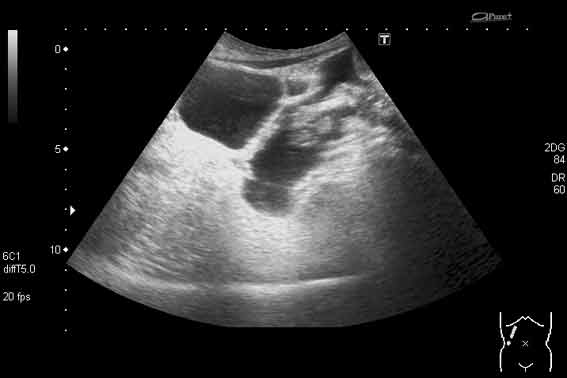

УЗИ, трихобезоар желудка. Gastric trichobesoar, ultrasonography.

Наблюдение наших коллег, работающих в педиатрии (valeriy.andilevko).

УЗИ, девочка 8 лет с ментальными расстройствами.

Безоар, проглоченный предмет ИМХО

Да, трихобезоар.